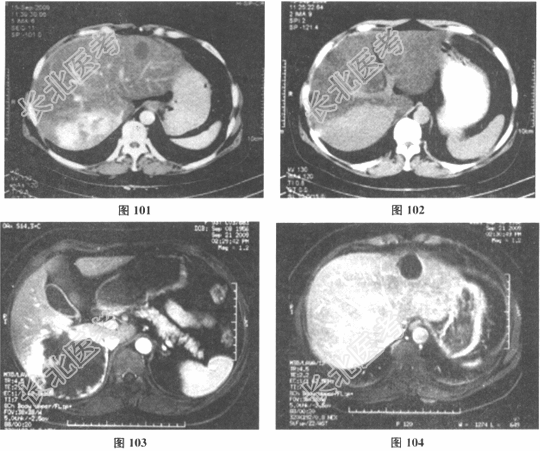

- 多项选择题2.[提示] 该患者增强CT和MRI检查提示肝脏有多发病变,其中右后叶的占位病灶约9.8cm×6.2cm×5cm大小; 结果见图101~图108。

请问该患者的临床诊断应考虑( ) A、右后叶肝恶性淋巴瘤

B、右后叶肝海绵状血管瘤

E、右后叶血管肉瘤

F、肝血管内皮细胞瘤

G、右后叶FNH